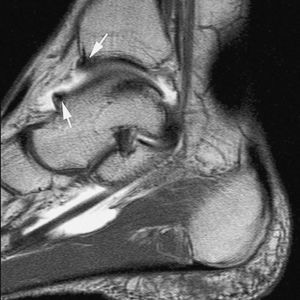

En la actualidad, la RMA es el método más eficaz en la valoración de las lesiones ligamentosas del tobillo. En la fase aguda, su indicación está limitada a aquellos casos en los que el cirujano plantea la realización de una reparación primaria --casos con lesión ligamentosa doble o en deportistas de alta competición--. Sin embargo, su principal indicación es la evaluación de la inestabilidad crónica de tobillo --tiene una sensibilidad del 100% y del 90% para las lesiones crónicas del LPAA y LPC, respectivamente (fig. 9), frente a una sensibilidad del 50% de la RM convencional--20,21.

Fig. 10.--Síndrome de choque antero-lateral. Corte axial de RMA potenciado en T1 que muestra un tejido fibroso irregular ocupando el receso capsular antero-lateral (flechas).